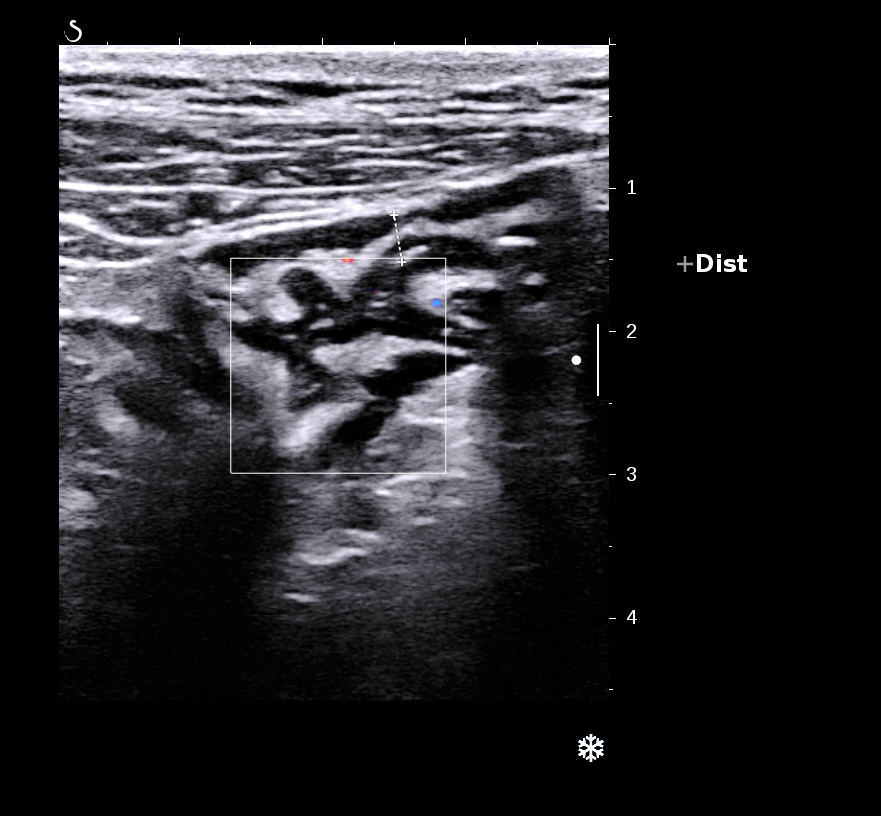

L'épaississement prédomine à la 3 ième couche hyperéchogène( > 1/3 de la paroi), il est continue, régulier, cironférentiel

La structure en couche est conservée

La graisse est peu infiltrée, l'activité doppler modérée.